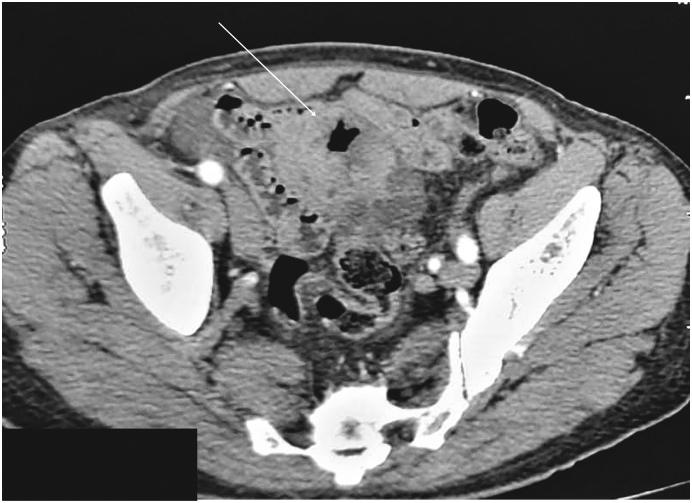

PRESENTATION OF CASE

A 65-year-old patient, with no comorbidities, presented with chronic and paroxysmal abdominal pain. Upper endoscopy and colonoscopy showed no abnormalities. Thoracoabdominal computed tomography (CT) revealed an ileal lobulated, heterogeneously enhancing solid mass measuring 6 cm. Laparotomy was performed. Findings showed a lobulated ileal mass. We made an enlarged ileal resection with end-to-end anastomosis. The postoperative course was uneventful. Histology and IHC stains concluded into ileal LMS. No relapse of the disease was noted during the 4-month follow-up.

一名65岁无合并症患者,出现慢性阵发性腹痛。上消化道内镜检查和结肠镜检查均未发现异常。胸腹部计算机断层扫描(CT)显示回肠有一个分叶状、强化不均匀的实性肿块,大小为6厘米。遂行剖腹手术。术中发现一个分叶状回肠肿块。我们进行了扩大的回肠切除术并端端吻合。术后过程顺利。组织学和免疫组化染色结果确诊为回肠LMS。在4个月的随访期间未发现疾病复发。